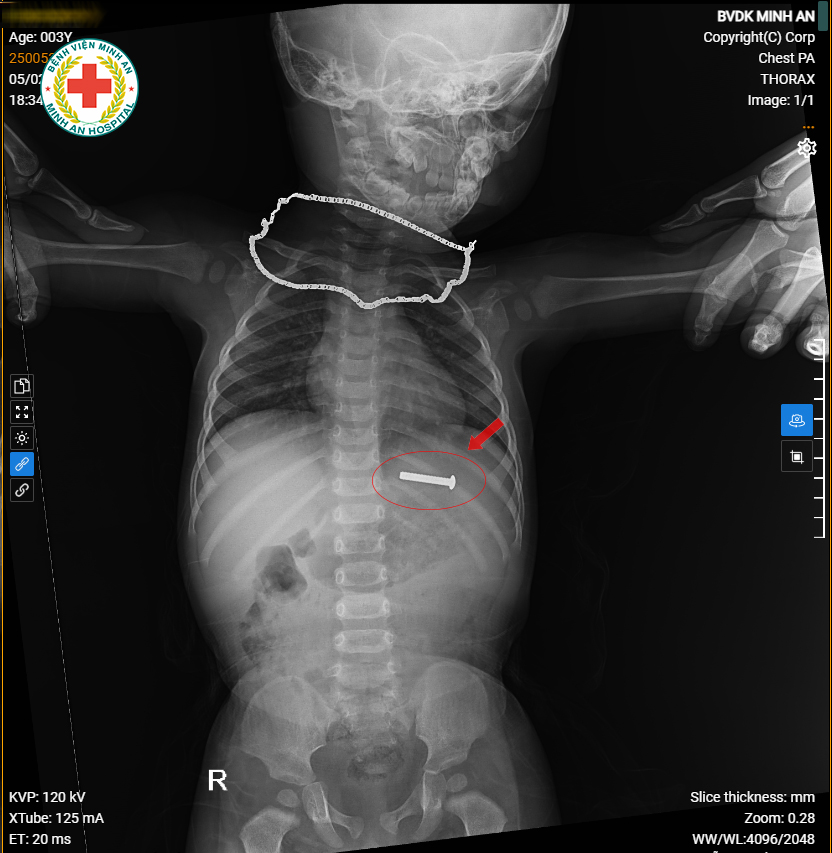

MỘT TRƯỜNG HỢP CHẤN THƯƠNG PHỐI HỢP PHỨC TẠP ĐƯỢC XỬ TRÍ KỊP THỜI VÀ HIỆU QUẢ

Trong số rất nhiều ca chấn thương khoa Ngoại – BVĐK Minh An tiếp nhận hằng tuần, có những trường hợp đòi hỏi không chỉ kiến thức chuyên môn sâu mà còn là sự phối hợp nhịp nhàng, thận trọng trong từng bước xử trí.